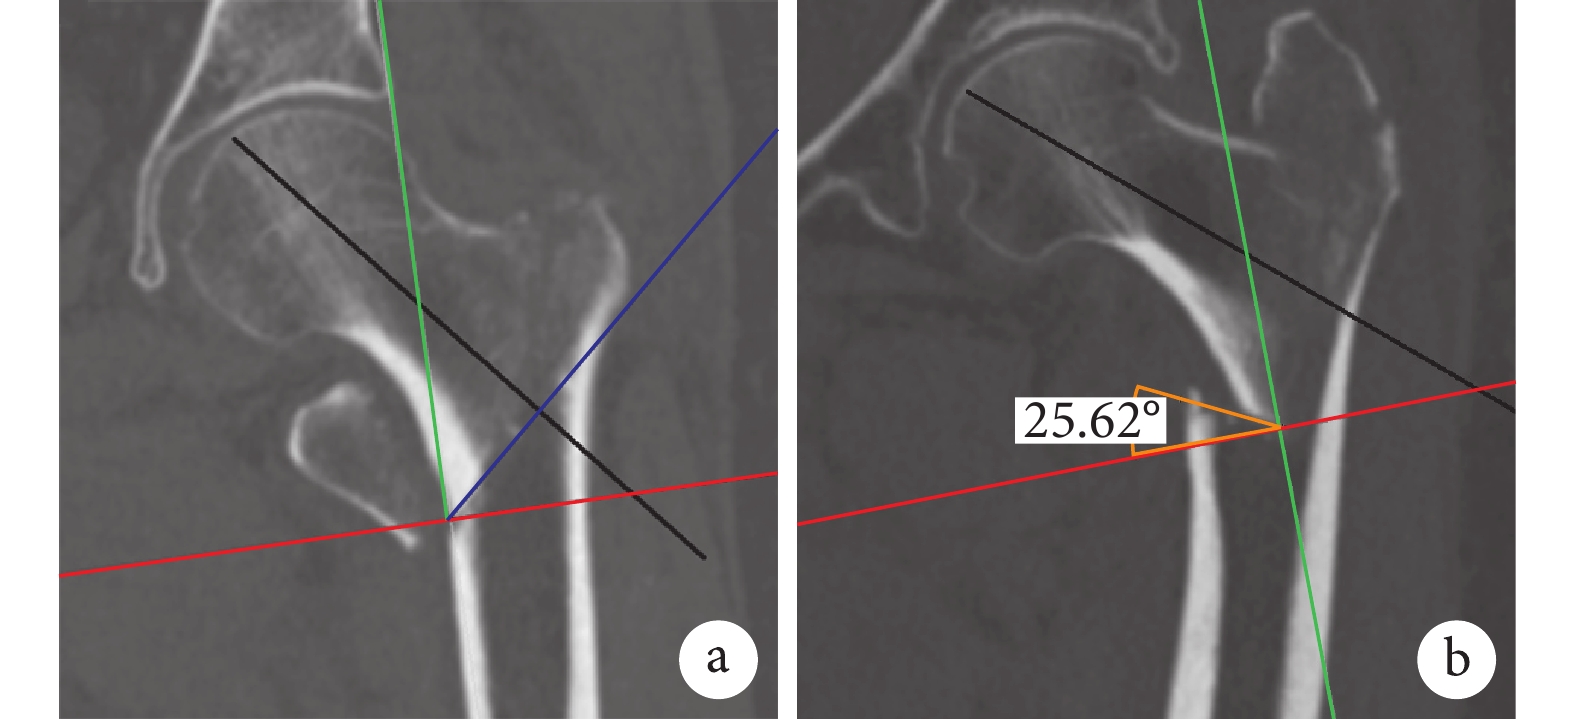

1.4 骨折前內側角骨皮質特征測量

對每個模擬復位后的圖像,先勾勒出前壁、內側壁的骨折線形態,確定前內側角骨皮質的測量點,即前壁骨折線與內側壁骨折線在前內側交匯所形成的交點。測量以下數據:前內側角處骨皮質的厚度,前壁骨折線與冠狀位水平線成角,內側壁骨折線與矢狀位水平線成角,內側壁可獲得支撐皮質寬度,并觀察前內側角處骨折近端的骨皮質斷面形態。見圖 1。

a:內側壁骨折線走行 b:前壁骨折線走行 c:前內側角處骨皮質的厚度 ∠d:前壁骨折線與冠狀位水平線成角 ∠e:內側壁骨折線與矢狀位水平線成角 f:內側壁可獲得支撐皮質寬度

Figure1. Sketch map of measurement points in anteromedial corner in intertrochanteric femur and data measurementa: Medial cortex fracture line b: Anterior cortex fracture line c: The thickness of anteromedial cortex ∠d: The angle of anterior fracture line and horizontal line ∠e: The angle of medial fracture line and horizontal line f: The width of medial supportable cortex